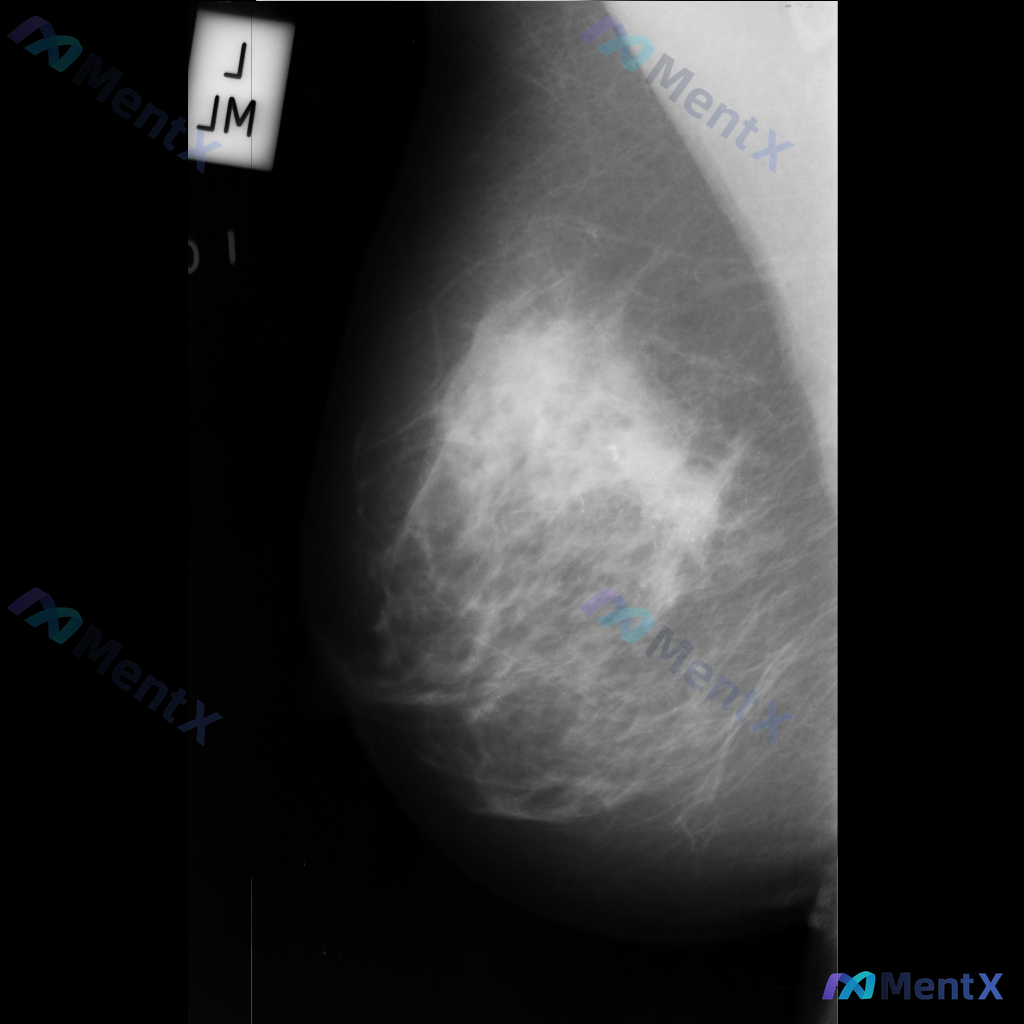

整理到一份乳腺钼靶的影像资料,想和大家讨论一下: - 钼靶所见:左侧乳腺中央偏下区域存在局限性结构扭曲,表现为纤维腺体组织排列紊乱、牵拉;未见明确的肿块或钙化灶。 - 背景:乳腺密度较高,属于不均匀致密型或极度致密型(ACR B或C型)。 目前这种结构扭曲的表现,大家会先往哪个方向考虑?下一步的评估...

整理到一份乳腺钼靶的影像描述资料,大家一起看看这种情况会先往哪个方向考虑? 影像为左侧乳腺内外斜位(MLO)钼靶图像,主要发现: - 存在一处边界模糊、形态不规则的致密影 - 内部密度不均,可见散在的微小点状高密度影(可疑钙化) - 致密影与周围腺体组织界限不清,可能伴有结构扭曲 单看这组影像描述,...